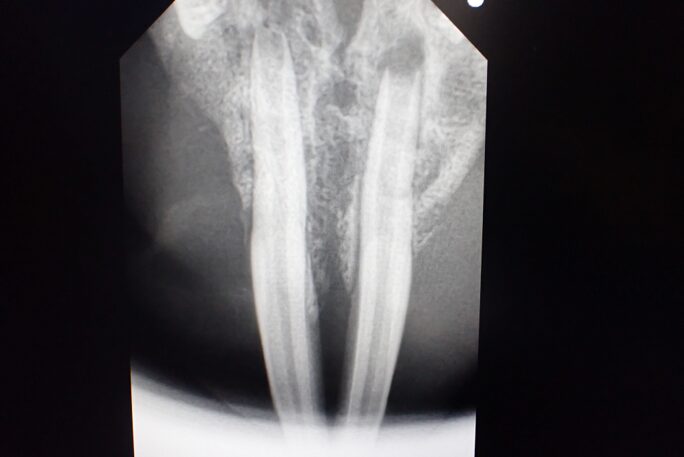

歯科用レントゲンでしっかり診断していきます。

下顎切歯根尖部の透過性亢進像、下顎に重度細菌感染がみられます